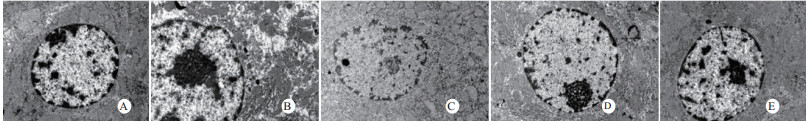

光镜下可见,假手术组肺泡大小形态均匀,结构清晰,肺泡腔内无出血和白细胞浸润;感染性休克组肺泡壁破坏严重,血管壁和肺泡间隔明显增厚;U50488H+感染性休克组大部分肺泡腔均匀一致,肺间隔略增厚,肺泡壁轻度水肿,但出血和白细胞浸润情况比感染性休克组明显减轻(图 1)。假手术组心肌细胞大小一致,排列整齐,核浆比正常,心肌细胞核呈椭圆型,胞浆均匀红染;感染性休克组心肌细胞肿胀,体积明显增大,细胞核大而异型,核内染色质固缩、边集,白细胞浸润明显增加;U50488H+感染性休克组多数心肌细胞形态相对正常,少数心肌细胞呈现脂肪变性(图 2)。假手术组肝细胞结构完整,肝小叶形态正常;感染性休克组肝细胞显著肿胀、呈空泡样和点状/小片状坏死;U50488H+感染性休克组肝细胞轻度肿胀,未见明显坏死灶、肝血窦扩张和炎性细胞浸润(图 3)。假手术组肾组织结构大致正常;感染性休克组肾小管细胞轻度水肿、空泡变性;U50488H+感染性休克组肾小管形态大致正常,间质无明显出血水肿(图 4)。

| A:假手术组,B:感染性休克组,C:U50488H+感染性休克组,D:nor-BNI+U50488H+感染性休克组,E:nor-BNI+感染性休克组 图 2 各组光镜下心肌组织病理学改变(HE×400) Fig 2 Histopathological features of myocardium(HE×400) |

扫描电镜下可见,假手术组肺泡形态完整,肺泡壁光滑;感染性休克组肺泡明显压缩畸形,肺泡隔肿胀、扭曲、隆起;U50488H+感染性休克组肺泡形态大致完整,少数肺泡壁肿胀受损(图 5)。透射电镜下可见,假手术组心肌细胞形态正常;感染性休克组心肌细胞溶解、坏死、肌纤维断裂;U50488H+感染性休克组心肌细胞大致正常,无明显坏死(图 6)。假手术组肝细胞形态正常,毛细胆管未见扩张;感染性休克组肝细胞大片坏死,毛细胆管明显扩张;U50488H+感染性休克组肝细胞形态大致正常,毛细胆管略扩张(图 7)。假手术组肾小管上皮细胞形态狭长,核卵圆形,位于基底部;感染性休克组肾小管上皮断裂,微绒毛缺失;U50488H+感染性休克组肾小管上皮细胞大致正常,微绒毛不平滑,但无明显坏死(图 8)。

| A:假手术组,B:感染性休克组,C:U50488H+感染性休克组,D:nor-BNI+U50488H+感染性休克组,E:nor-BNI+感染性休克组 图 6 心肌细胞透射电镜检查(×10 000) Fig 6 Transmission electronic microscopic photos of myocardial cell(×10 000) |